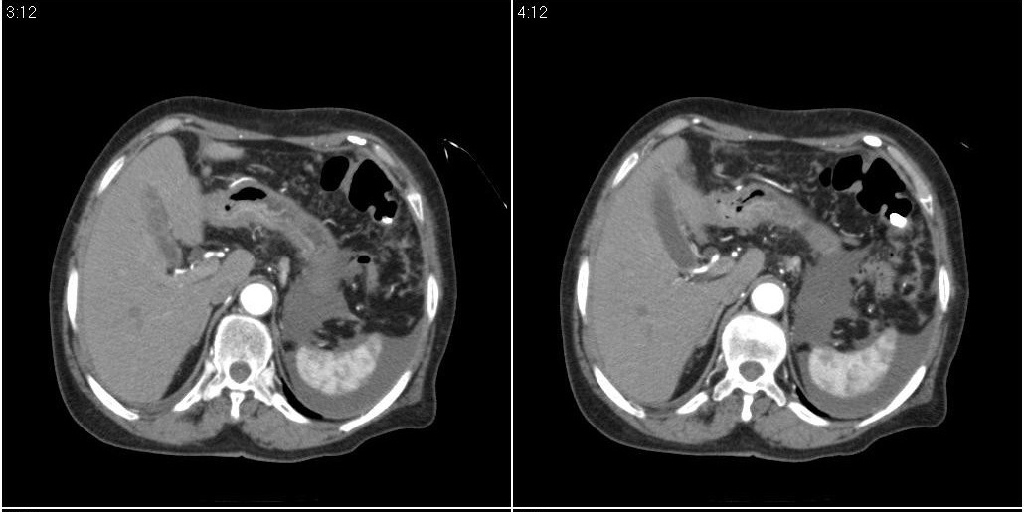

胆囊有问题么,是结石么?胆囊内异常密度平扫30hu左右,增强各期无变化。

胆囊内稍高密度影,无强化,胆囊壁增厚,周围见低密度影,右侧膈肌角及脾周水样密度,支持胆囊泥沙样结石,胆囊炎、胆囊窝积液,胸腹水。

1)胆囊炎,胆结石;胆囊新生物待排。2)胆囊窝积液。3)腹水。4)右侧少量胸腔积液。